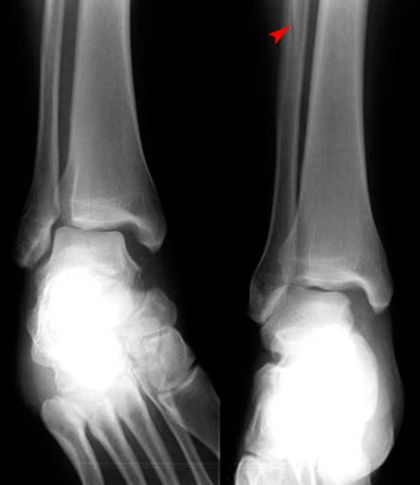

踝关节骨折

疼痛科怎么理疗疼痛科医生、康复理疗科医生、针刀针灸医生应掌握的常见骨科疾病X光片_https://www.jmylbn.com_新闻资讯_第39张

三踝骨折

疼痛科怎么理疗疼痛科医生、康复理疗科医生、针刀针灸医生应掌握的常见骨科疾病X光片_https://www.jmylbn.com_新闻资讯_第40张